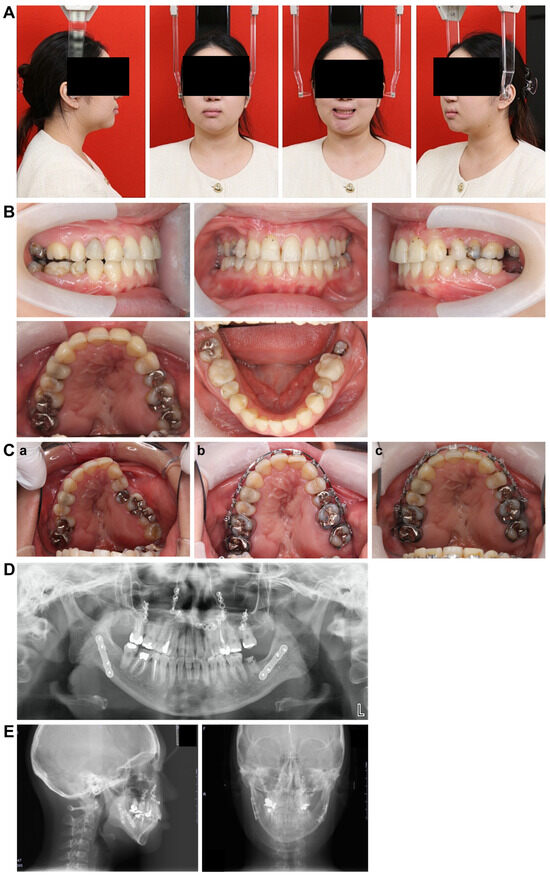

3.1. Initial Facial Findings (Figure 1A)

The frontal view showed facial asymmetry, with the left corner of the mouth elevated and a canted occlusal plane tilted upward on the left side when smiling. The lateral view revealed a concave profile with protrusions on the upper and lower lips. The esthetic line (E-line) measurements were −2.0 mm and +7.0 mm for the upper and lower lips, respectively, indicating a greater lower facial height relative to the upper facial height, suggesting an imbalance in vertical proportions.

Figure 1.

Pre-treatment record. (A) Facial photographs. (B) Intraoral photographs.

3.2. Intraoral Photo at First Visit (Figure 1B)

The left maxillary dental arch was constricted and exhibited a crossbite. The anterior maxillary and posterior arch widths were 25.1 mm and 38.0 mm, respectively, with notable constriction in the anterior width. The molar relationship was classified as Angle Class III on the right side and Angle Class II on the left side. The overbite was +1.5 mm and the overjet was +2.0 mm. The arch length discrepancy was −3.0 mm and −3.9 mm in the maxilla and mandible, respectively, with mild crowding observed. The maxillary left lateral incisor was congenitally missing, and the mandibular right lateral incisor showed lingual displacement. Furthermore, oral hygiene was poor, with multiple prosthetic restorations in both the upper and lower jaws. In addition, the patient reported weak occlusal force on the left side and was unable to chew properly.